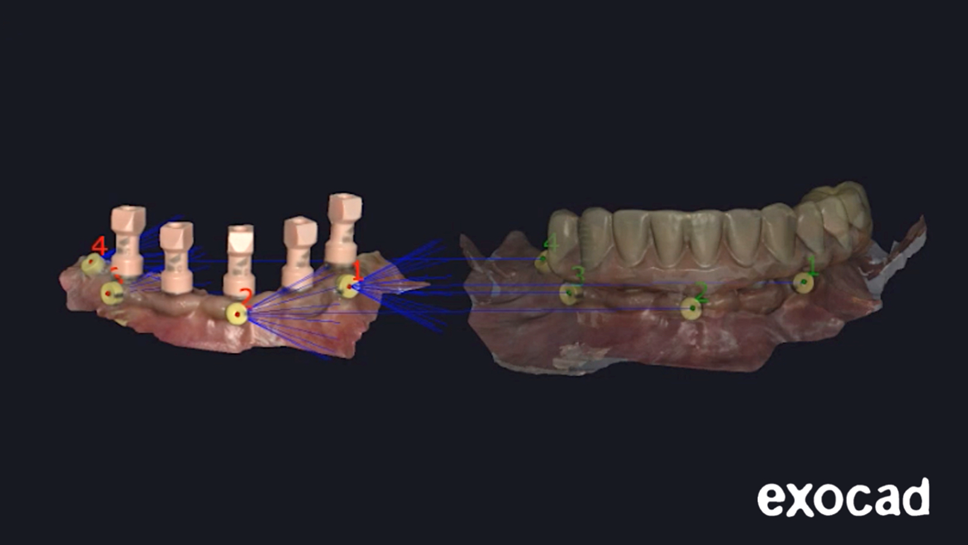

7- Importe os arquivos digitais salvos para o software CAD (DentalCAD; Exocad GmbH) e faça o alinhamento dos arquivos digitais utilizando os marcadores como pontos de referências (Figura 6).